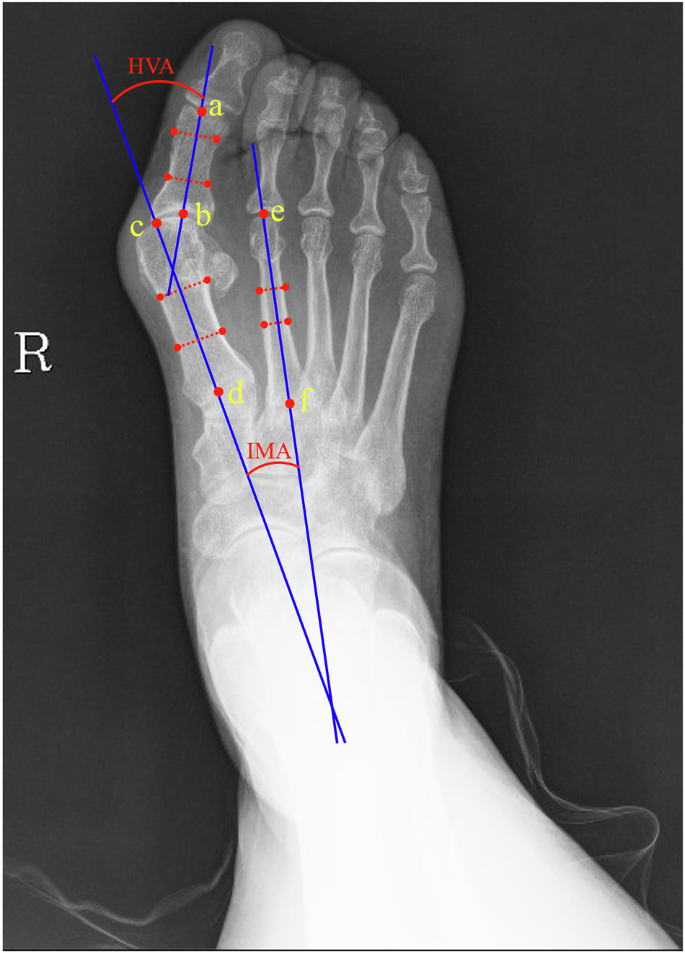

HVA, IMA and line segments were annotated in accordance with the standards set by AOFAS4,5, as shown in Fig. 2. First, two parallel lines (red dashed lines) were drawn for the great toe, the first metatarsal, and the second metatarsal. Second, the center lines of each phalanx (blue solid lines) were drawn through the midpoints of the two parallel lines. Third, the intersection points of these center lines with the ends of each phalanx were identified and served as the endpoints for the corresponding phalanx line segments Finally, the HVA and IMA were calculated using the labeled endpoints of each phalanx. If discrepancies between HVA and IMA annotations by Labelers A and B were less than 1°, Labeler B’s annotation was selected. If errors exceeded 1°, Labeler C reviewed the task. If Labeler C’s annotations differed by less than 1° from either Labeler A or B, Labeler C’s annotations were accepted. Otherwise, Labeler D’s annotation was considered final. An example of images and their annotations from HVAngleEst is shown in Fig. 3.

The workflow for HVA, IMA, and line segments labeling: (1) Two parallel lines (red dashed lines) were drawn to annotate the great toe, the first metatarsal, and the second metatarsal. (2) The midpoints of these parallel lines were joined to create a straight line. (3) The points where this straight line intersects the edge of the phalanx defined the line segment points for that phalanx. The points (a, b), (c, d), and (e, f) correspond to the line segments of the great toe, the first metatarsal, and the second metatarsal. (4) HVA and IMA were calculated by the endpoints of each phalanx.